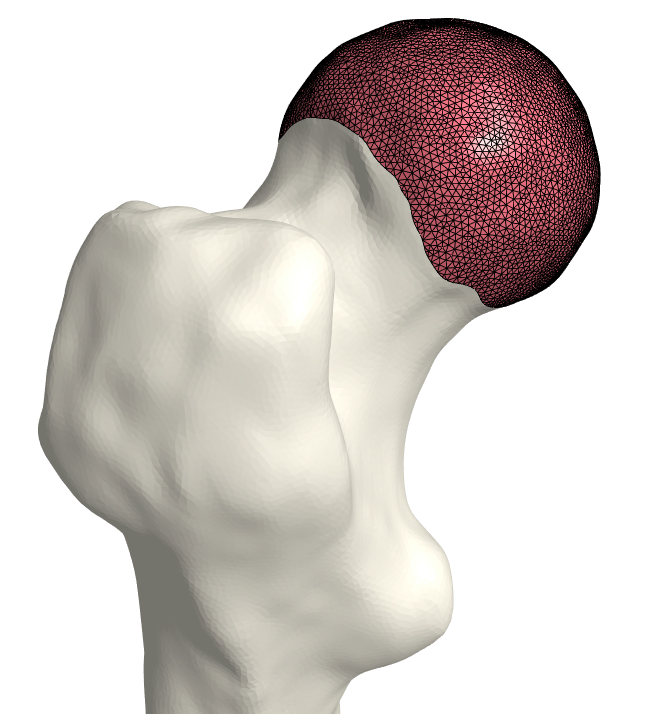

3.3 Extrusion

As this is a trait of healthy cartilage, we expect the generated geometry to have a high degree of congruence. We extrude vertices based on the minimal distances between the bones and choose the midpoint as the extrusion height to guarantee congruence. This approach ensures the conformity of the cartilage-cartilage interface. We want the shape to thin out as we get further away from the contact center to mimic the real cartilage shape. The faces to extrude, are chosen to be a copy of the bone-attached estimate, (𝒱CD,CD)superscriptsubscript𝒱𝐶𝐷superscriptsubscript𝐶𝐷(\mathcal{V}_{C}^{D},\mathcal{F}_{C}^{D}), and are denoted by (𝒱CE,CE)superscriptsubscript𝒱𝐶𝐸superscriptsubscript𝐶𝐸(\mathcal{V}_{C}^{E},\mathcal{F}_{C}^{E}): the extruded geometry. We assign height to each vertex in the extrusion region, 𝐯𝒱CE𝐯superscriptsubscript𝒱𝐶𝐸\mathbf{v}\in\mathcal{V}_{C}^{E}, based on the smallest distance to the second bone as,

𝐯𝐯+12𝐧min𝐯S𝒱S𝐯𝐯S2\displaystyle\mathbf{v}\leftarrow\mathbf{v}+\frac{1}{2}\mathbf{n}\min\limits_{\mathbf{v}_{S}\in\mathcal{V}_{S}}\lVert\mathbf{v}-\mathbf{v}_{S}\rVert_{2} (3)

where 𝐧𝐧\mathbf{n} is the unit outward normal direction of vertex 𝐯𝐯\mathbf{v}. For the pelvis, the faces we extrude are a copy of the bone-attached region. As the pelvic bone-attached region does not need growing, we shrink the set of faces to be extruded by applying the same trimming approach as described in Section 3.1. We then extrude the reduced set of faces (Equation (3)), using the distances from the pelvis to the femur.

Refer to caption

(a) Femoral cartilage.

(b) Femoral cartilage.

(c) Pelvic cartilage.

Figure 3: The final cartilage generated by our method for a femur (a), (b) and a pelvis (c). Notice how the cartilage aligns with the anatomical lines.